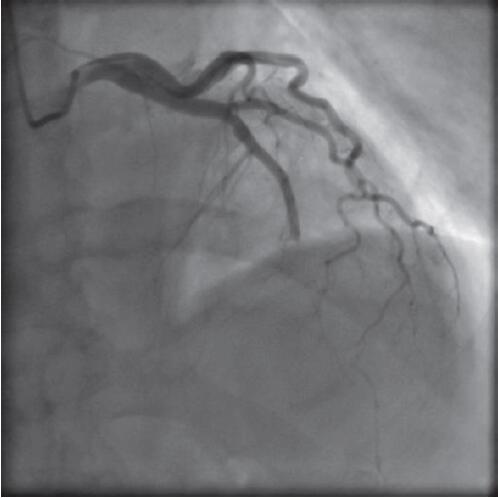

300mg嚼服,联系心内科导管室。转入导管室后行急诊PCI,冠脉造影发现前降支中段完全闭塞(图4),和预想的一样,但观察其闭塞部位类似树枝折断样的改变,考虑为血栓栓塞所致,立即行导管抽吸,抽出新鲜血栓(图5)。

图4 冠脉造影提示前降支中段闭塞